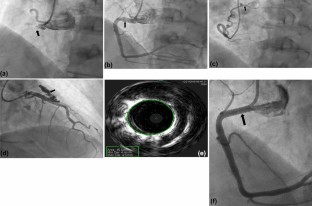

Fig. 1

Video 1a Coronary angiogram: left anterior oblique view of RCA was notable for proximal RCA CAA with visible thrombus within the aneurysm sac (arrow) in a patient with acute coronary syndrome. (AVI 2642 kb)

Video 1b Coronary angiogram was notable for coronary fistula between Conus branch of RCA and pulmonary artery. (AVI 2134 kb)

Video 1c Intravascular ultrasound (IVUS) shows true lumen in RCA proximal. (AVI 17600 kb)

Video 1d Coronary angiogram: left anterior oblique view of RCA after insertion of covered 4.5 mm x 19 mm stent (arrow) to the proximal RCA. RCA proximal thrombus and obstruction resolved, aneurysm excluded, and TIMI 3 flow was obtained. (AVI 3788 kb)